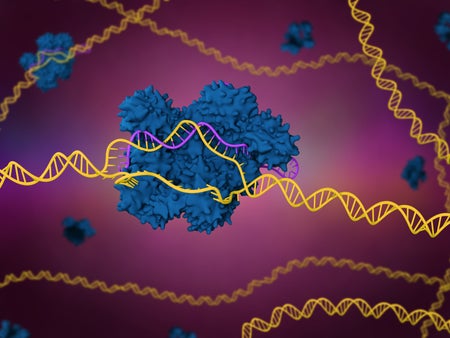

In First, Scientists Use CRISPR for Personalized Cancer Treatment

The “most complicated therapy ever” tailors bespoke, genome-edited immune cells to attack tumors